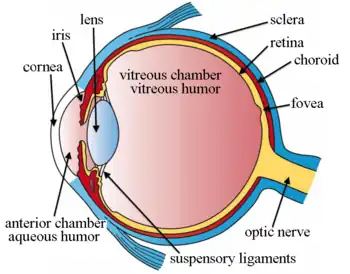

Structures of the eye labeled

Structures of the eye labeled This image shows another labeled view of the structures of the eye

This image shows another labeled view of the structures of the eye